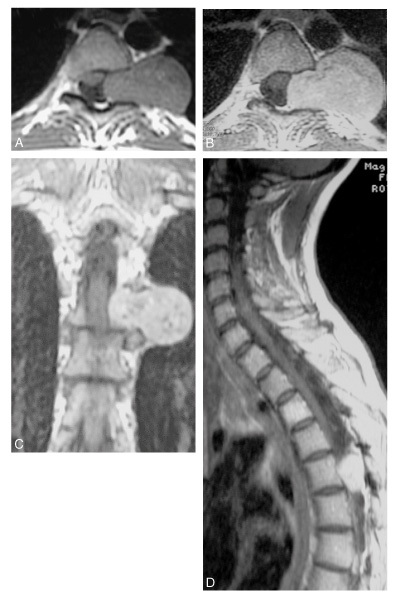

Diagnostic?

Neurinome en sablier T5 -T6 gauche

(dans l’ordre de gauche à droite et de haut en bas: abcd)